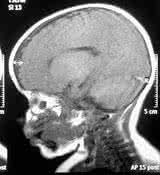

流行性乙型脑炎(简称乙脑)的病原体1934年在日本发现,故名日本乙型脑炎,1939年我国也分离到乙脑病毒,解放后进行了大量调查研究工作,改名为流行性乙型脑炎。本病主要分布在亚洲远东和东南亚地区,经蚊传播,多见于夏秋季,临床上急起发病,有高热、